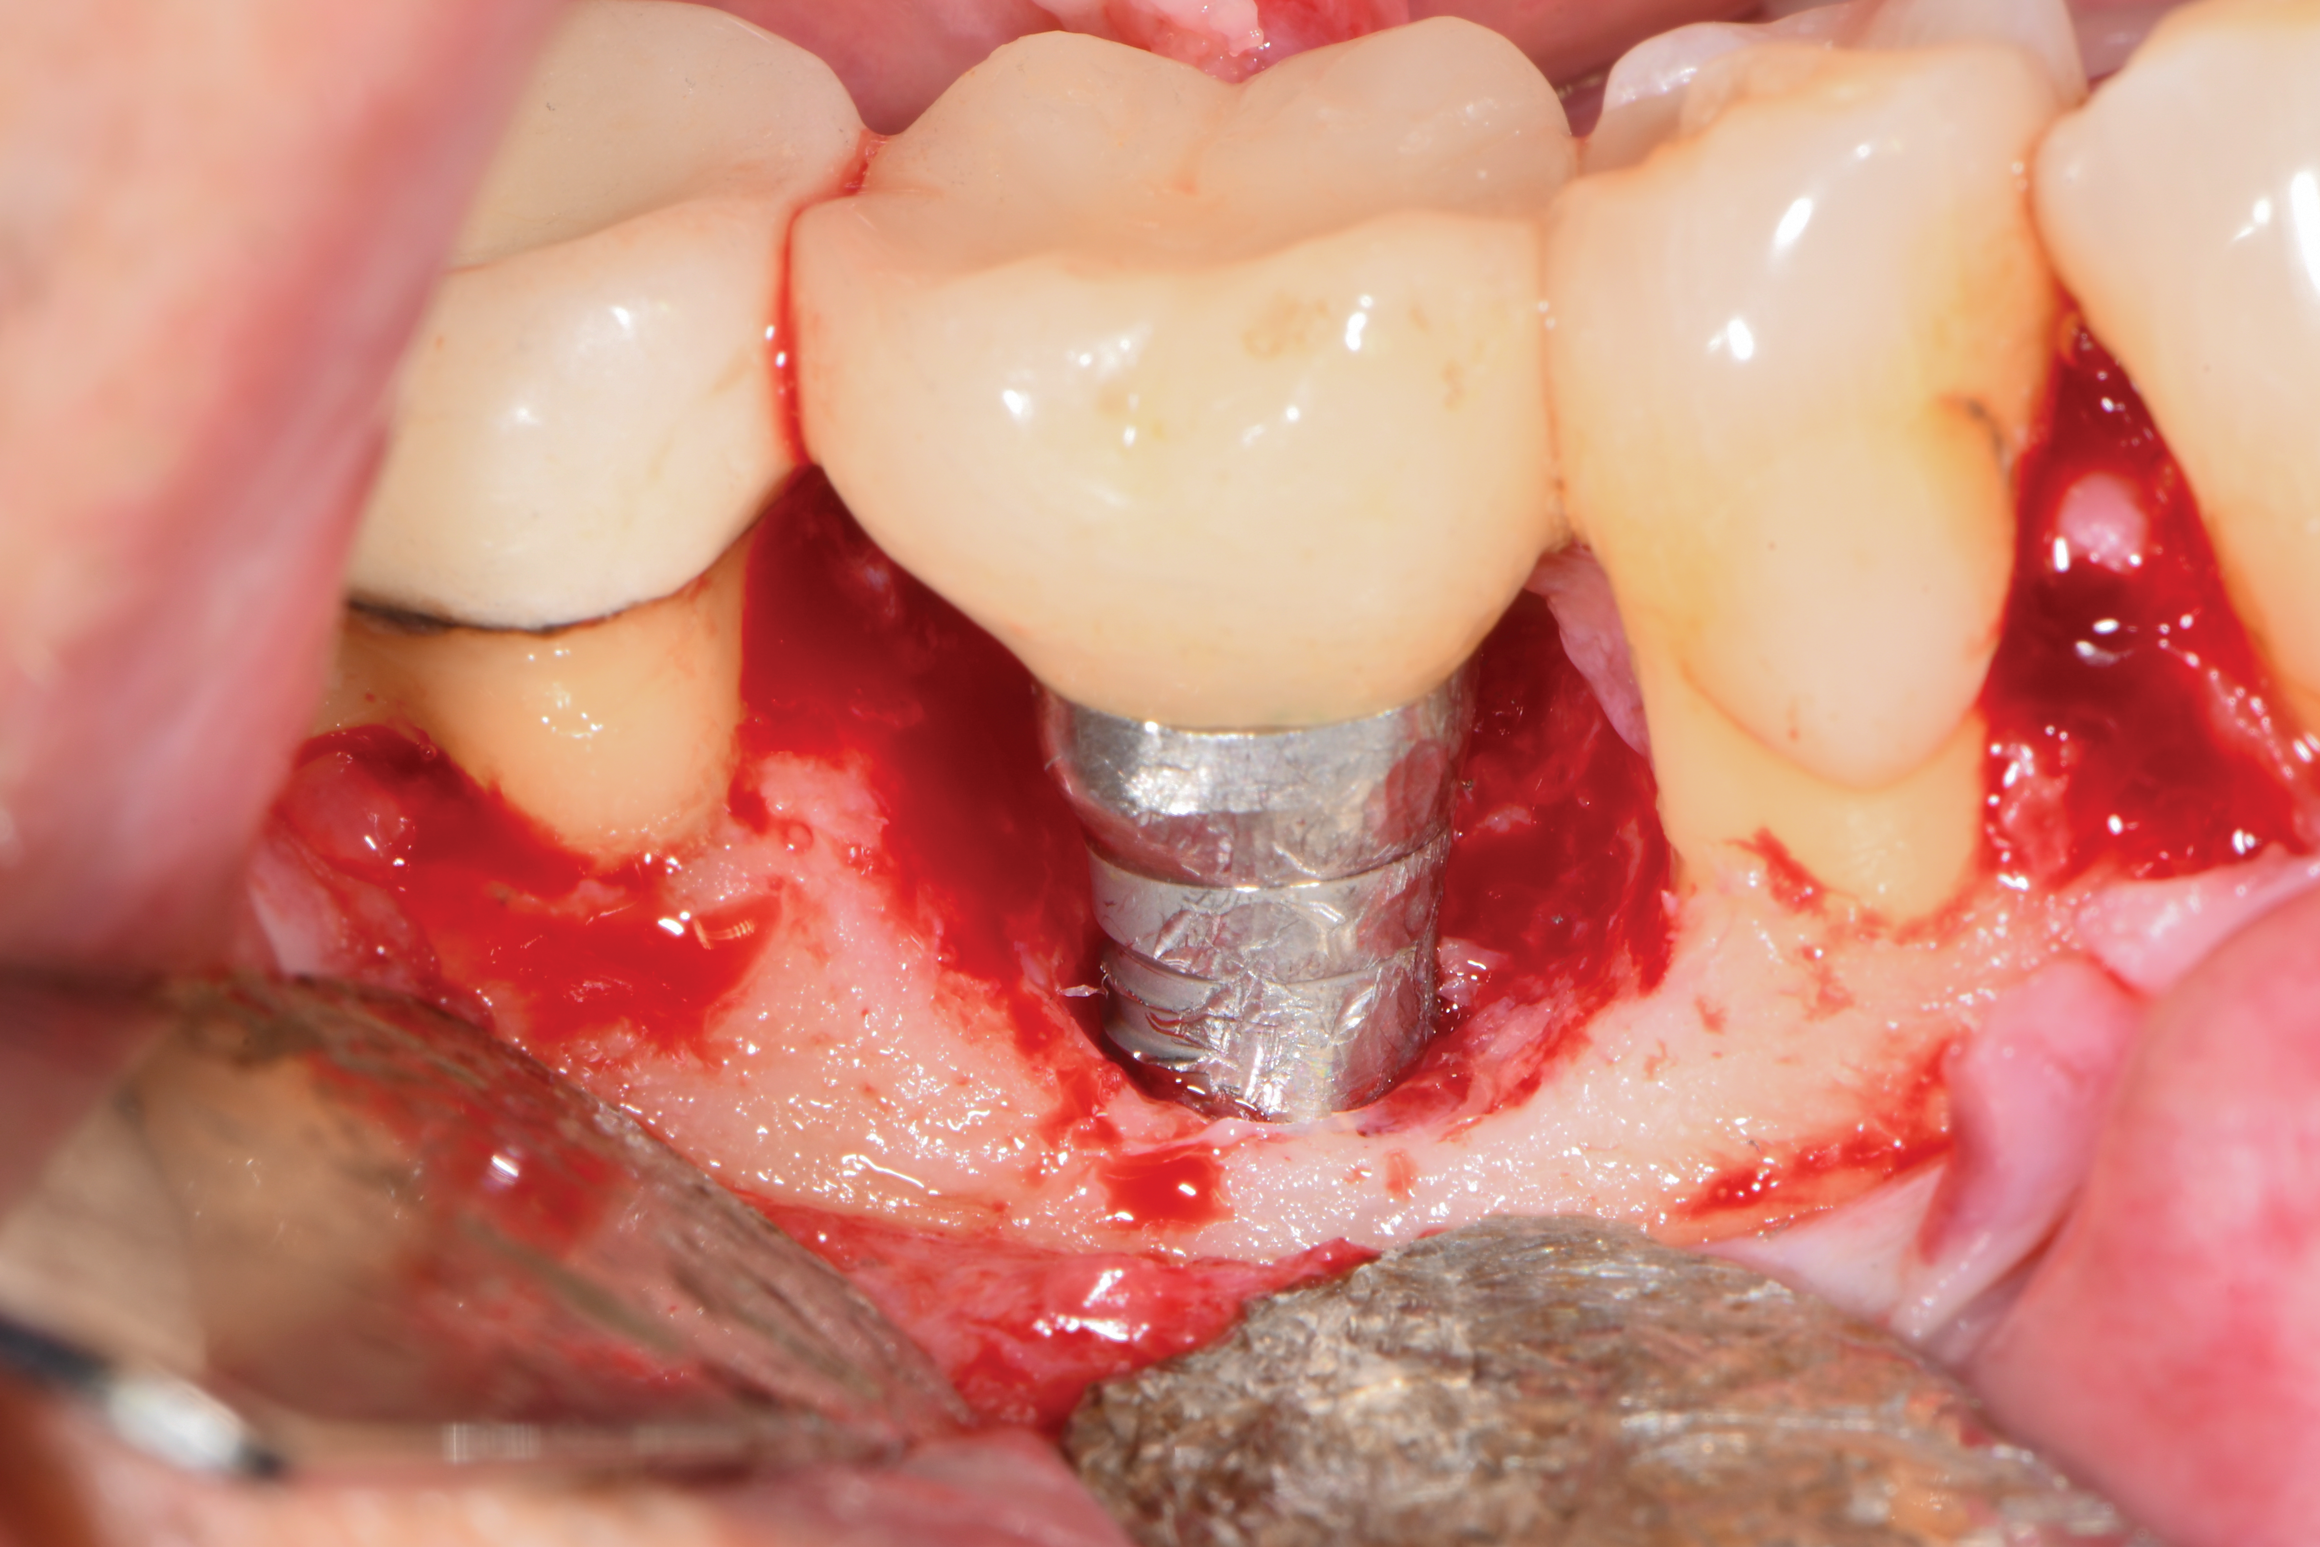

After local anesthesia was administered, full-thickness flaps were elevated from the buccal and lingual aspects of tooth No. 27 to the distobuccal and lingual aspects of tooth No. 31. Removal of granulomatous tissue from the implant site allowed visualization of a combination lesion with two walls at the distal and two to three walls at the mesial with a circumferential configuration on the lingual (Figure 12). The surface was initially treated with a 50% solution of citric acid for 30 seconds, which was burnished on with cotton pellets followed by thorough rinsing with sterile saline. This was followed by implantoplasty using 12-fluted followed by 30-fluted surgical-length finishing burs that provided access to the base of the defect. Because the crown was cemented, which obviated access, a matte-like surface could not be achieved; thus, the goal was to reduce the threads and remove the outer affected surface to expose fresh titanium (Figure 13). At this stage, the implant was wiped again with citric acid and rinsed with sterile saline.

Fig 13. Implantoplasty was completed. Some bleeding at the distal obscured one thread that was impossible to plasty. The surface was subsequently wiped with citric acid prior to grafting.

Figure 13